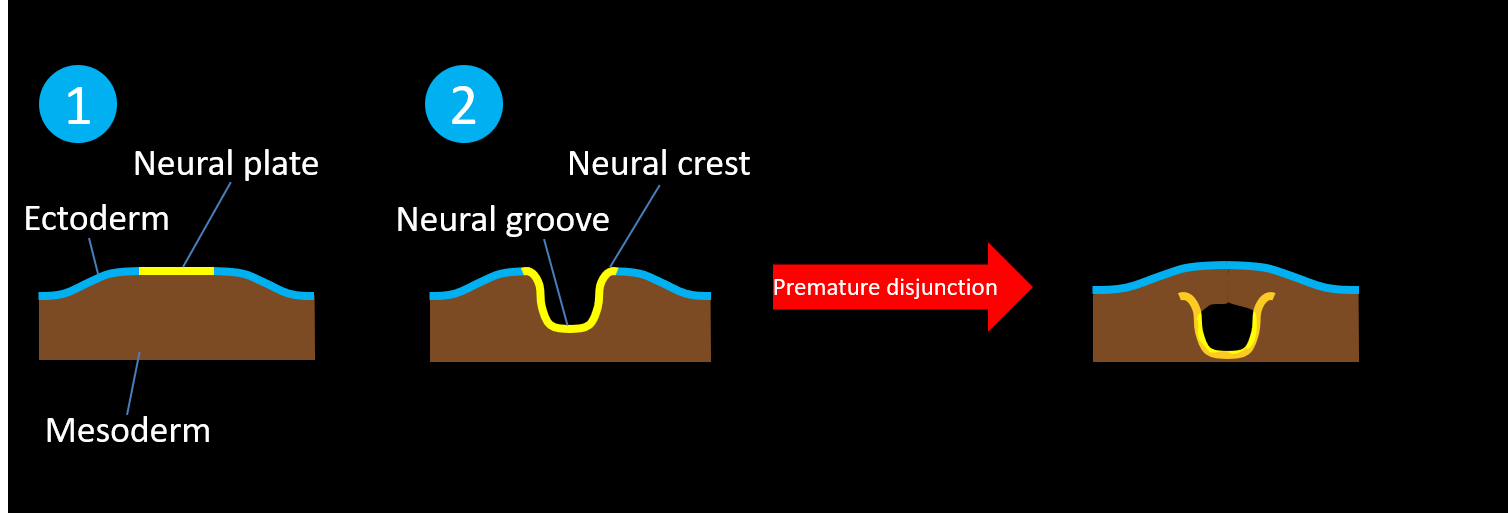

- Premature disjunction results in closed neural tube defects (i.e. defects with skin covering) where mesodermal elements are interposed within an incompletely closed neural tube that separates from the ectoderm, including:

- Lipomyelomeningocele – lipoma-placode interface located outside of the spinal canal

- Lipomyelocele – lipoma-placode interface located inside of the spinal canal

- Meningocele – meningeal lining herniates through a spinal canal defect without herniation of neural elements

- Terminal myelocystocele – syringocele herniates into a meningocele

- Premature disjunction results in closed neural tube defects (i.e. defects with skin covering) where mesodermal elements are interposed within an incompletely closed neural tube that separates from the ectoderm, including:

-

-

-